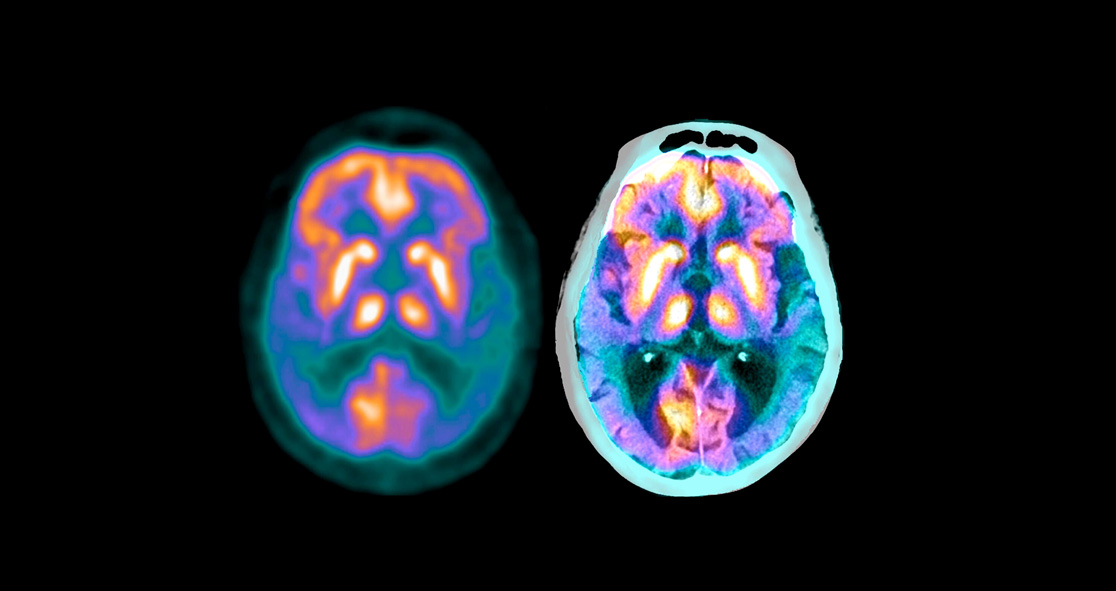

The researchers also looked at donanemab’s impact on the accumulation of tau proteins and amyloid-beta plaque, which are seen in patients with Alzheimer’s disease.

After 52 weeks, nearly 60% of participants who received the drug had reached amyloid-negative status. At 76 weeks, amyloid plaque levels decreased in those who received the drug.